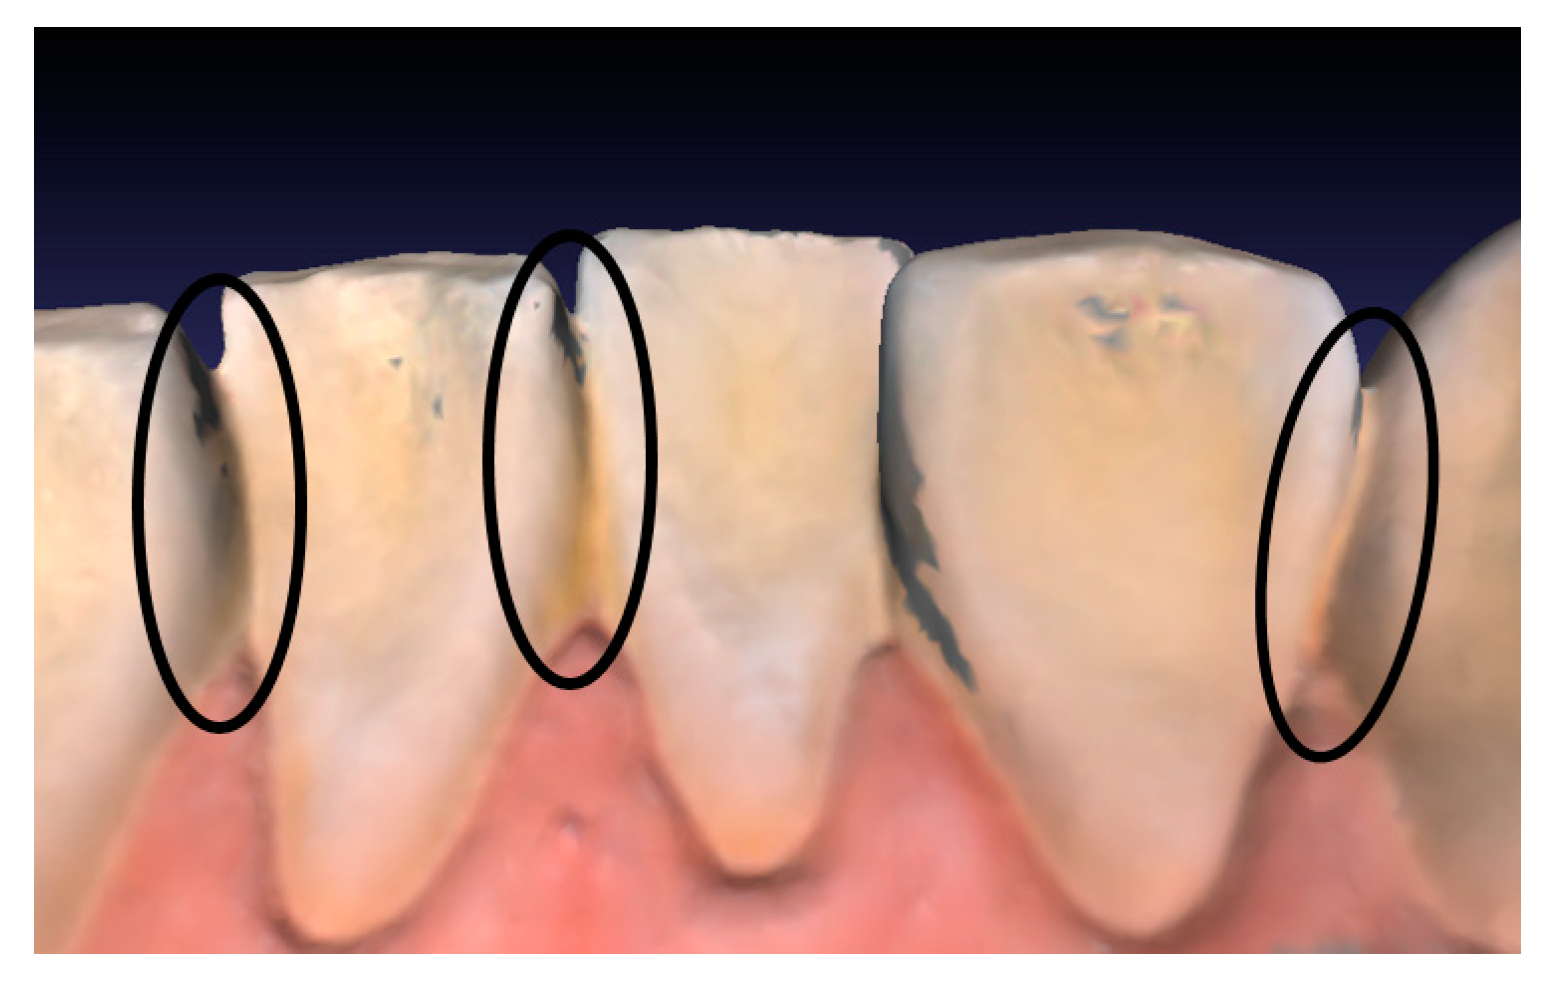

1.1.2. Tooth Segmentation

1.3. Motivation and Contributions of This Paper

1.3.3. Goals

2. Proposed Method

2.1. Overview